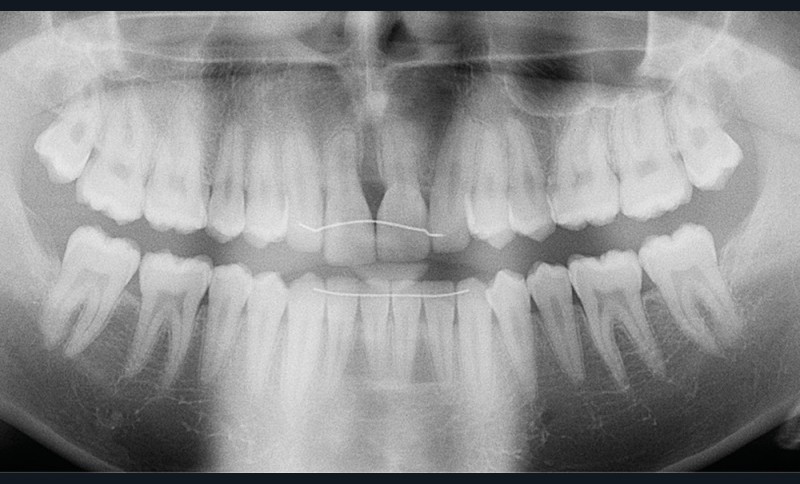

Antony, 11 ans se présente initialement pour une demande esthétique concernant ses deux incisives centrales qu’il trouve trop grosses (fig. 1a-c).

Le profil est convexe et associé à une inocclusion labiale au repos. Il s’agit d’une classe II squelettique sur un schéma facial normodivergent. Les rapports occlusaux sont de classe II bilatérale (complète au niveau molaire) avec des incisives inférieures vestibulo-versées. La 21 est géminée et la 11 vraisemblablement fusionnée avec un germe surnuméraire, sans altération de la formule dentaire. Du fait du diamètre mésiodistal fortement augmenté des incisives centrales, et du manque de place à l’arcade maxillaire qui en découle, les 12 et 22 sont en inversé d’occlusion en palato position. Les 53 et 63 sont persistantes sur l’arcade avec une inclusion en transposition incomplète de la 13, dont la cuspide se situe entre la racine de la 12 et celle de la 11 résorbée (fig. 1d-g).